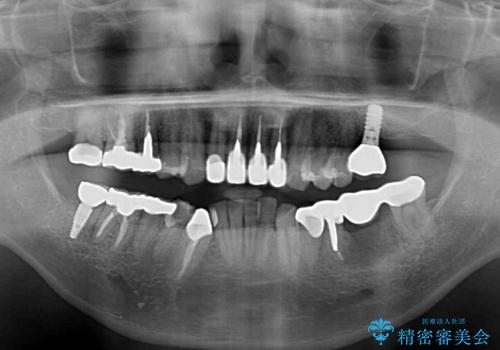

欠損している歯や、割れてしまって抜歯の必要な歯などがあり、咬合力が強いため欠損部はインプラント補綴を前提に治療を行うこととしました。

しかしながら、左下の抜歯部位は骨欠損が著しく大きく、多大な垂直的骨造成を要するため、3歯を支台としたブリッジによる補綴治療とし、右下のみをインプラント補綴としました。

小さい修復物の銀歯が装着されている歯はセラミックインレーにて、その他はオールセラミッククラウンにて補綴治療を進めることとしました。